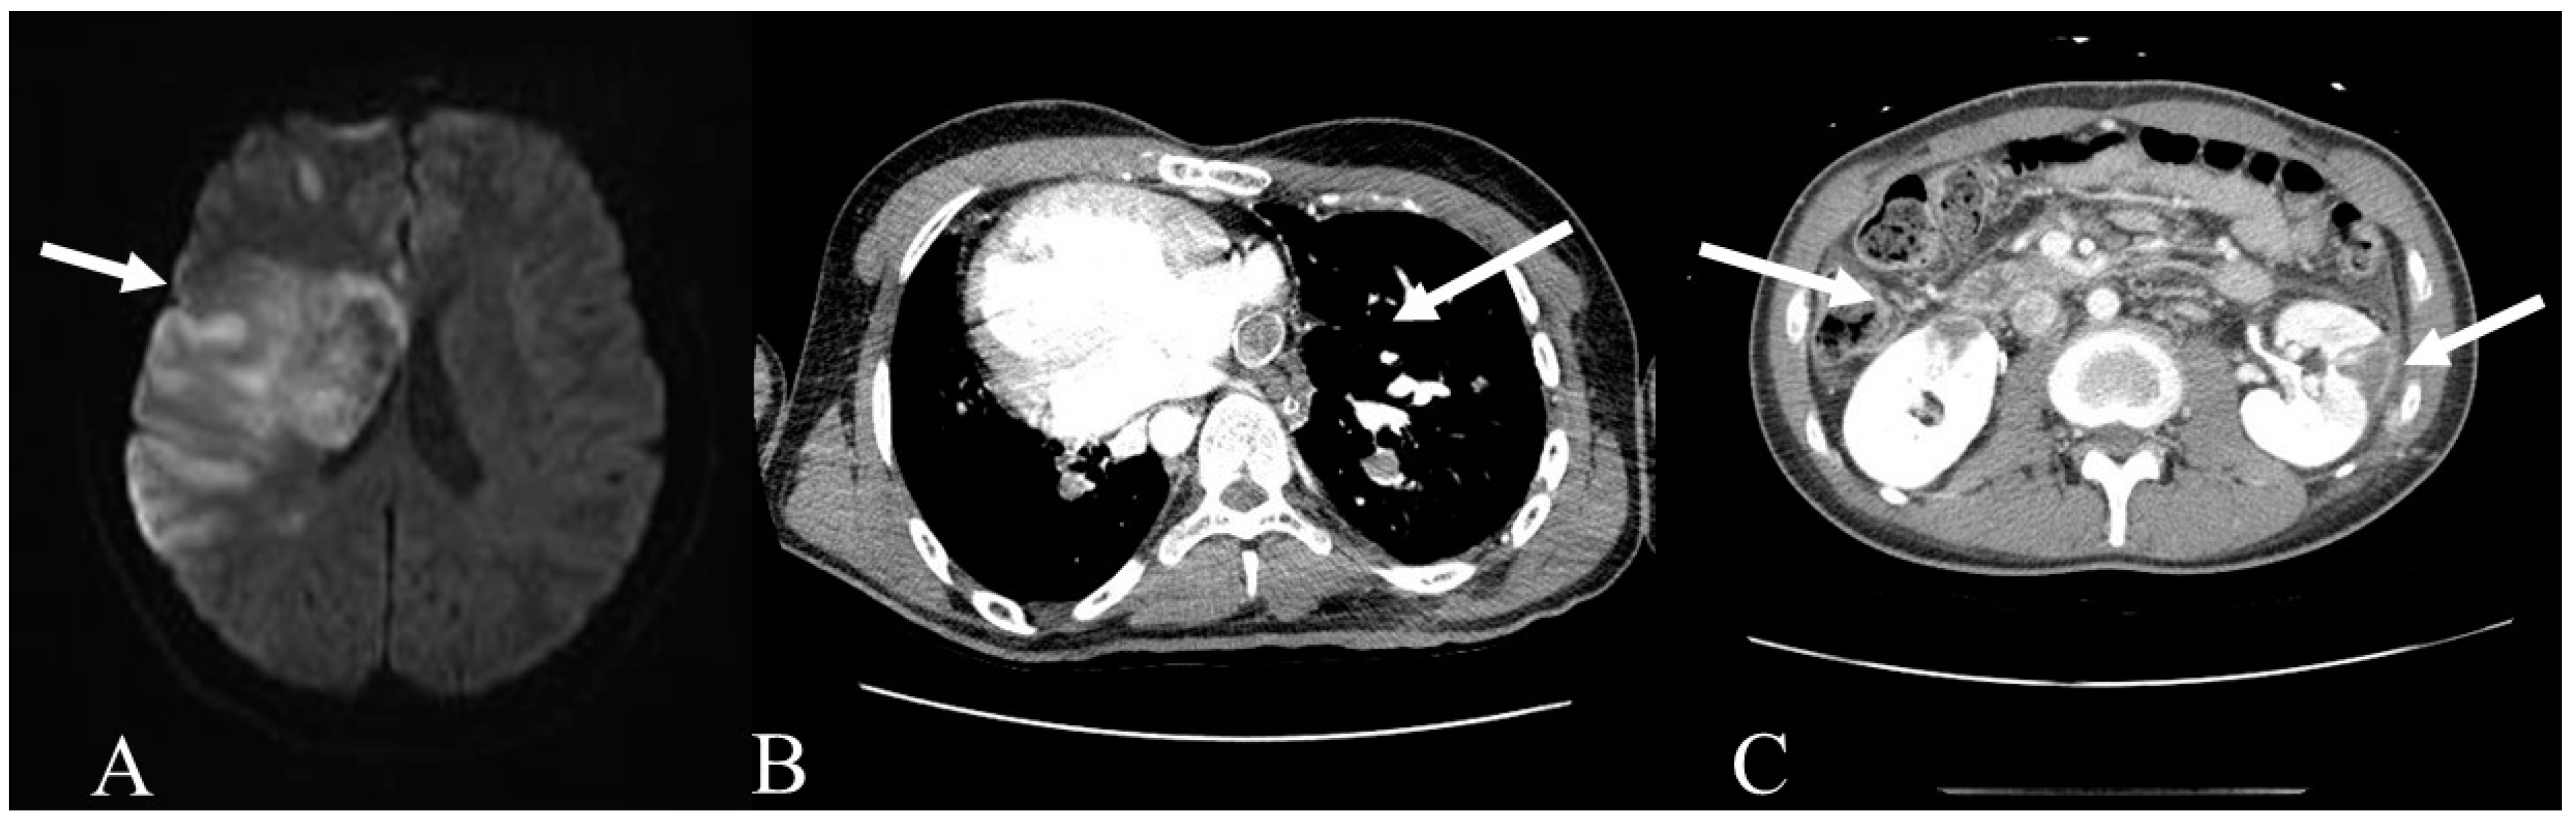

2. Case Report